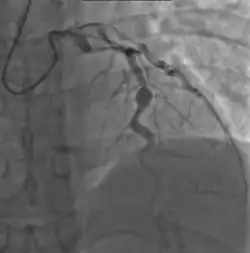

Angiography showing ectatic LAD, with largest aneurysm = 6.5 mm in diameter

Since no specific laboratory test exists for Kawasaki disease, diagnosis must be based on clinical signs and symptoms, together with laboratory findings.[9] Timely diagnosis requires careful history-taking and thorough physical examination.[119] Establishing the diagnosis is difficult, especially early in the course of the illness, and frequently children are not diagnosed until they have seen several health-care providers. Many other serious illnesses can cause similar symptoms, and must be considered in the differential diagnosis, including scarlet fever, toxic shock syndrome, juvenile idiopathic arthritis, and childhood mercury poisoning (infantile acrodynia).[120]